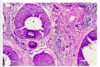

Vad visar bilden?

Normalt endometrium